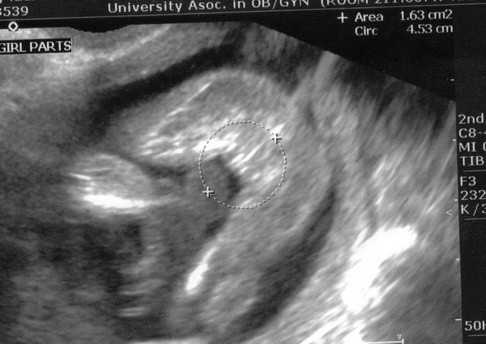

sonogram-gender

there was a thread recently that provided a link which showed pictures of a babies gender on a sonogram.

I had my amnio today. My decided to lay on it's belly for the most part. However, at one point stretched out it's legs and then made the number 4 w/them. I don't know if you can tell anything at 16w1d but I'd like to compare...

here's mine at 16w6d Image Attachment(s):

thank you very much. Those were the sites. Unfortunately I can't tell anything. My sono shows 2 white dots (lines) that I can see.

Teaches me to be nosey...my DH and I don't want to know. i just wanted to "cheat" a little bit.